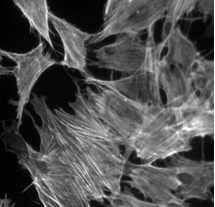

1、细胞生物学:用于观察细胞结构、动态和相互作用。